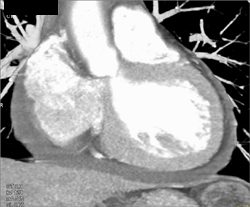

Cardiac Vein and Right Coronary Artery